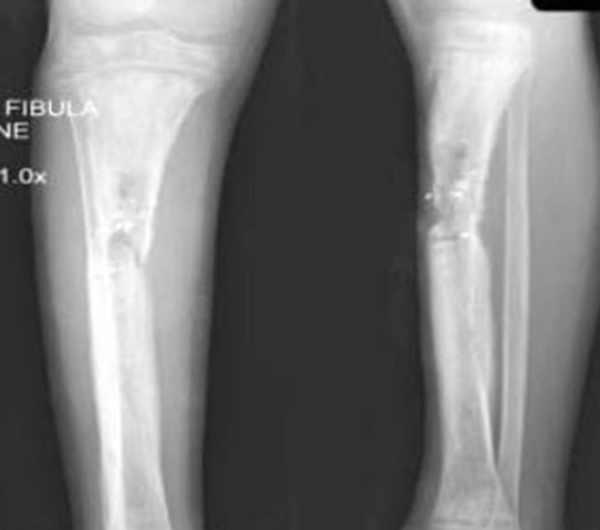

查瞅:厚皮性骨膜病的X线查瞅瞅来胫骨、腓骨、桡骨、尺骨等部位有增素性骨膜炎、充溢性骨膜增厚。

诊疗:依据皮肤及骨骼X线查瞅睹增素性骨膜炎、充溢性骨膜增厚的典范临床转变可作出诊疗。